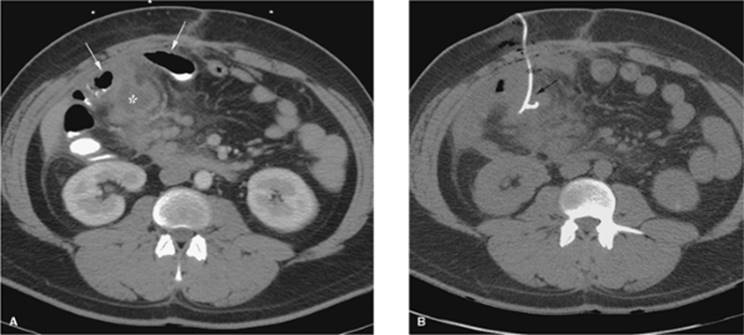

Abdominal Paracentesis

Ultrasound or CT guidance can be used to drain diffuse or loculated fluid collections in the abdomen. In most cases, ultrasound is sufficient and can be performed at the bedside. The site of maximal fluid collection is localized without evidence of intervening loops of bowel, and this area is marked and prepped. The procedure can usually be performed with local anesthesia without sedation. The preference at our institution is to use the 6 French Safe-T-Centesis catheter kit. This drainage procedure can be performed for diagnostic and/or therapeutic purposes. When performed as a therapeutic procedure, the catheter and tubing can be connected to either a three-way stopcock and drainage bag or to a 1-L vacuum bottle system. Removal of volumes greater than 5 L can lead to volume redistribution and may require IV albumin infusion (Fig. 35.8A, B).

Figure 35.8. Abdominal paracentesis. A: Initial position shows a segment of bowel blocking access to the perihepatic fluid. B, segment of bowel; L, liver; asterisk, fluid. B: Slight change in transducer position yields a safe pathway for drainage.